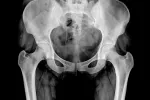

• Dolor esquelético difuso: es el síntoma más típico de la osteomalacia. Las zonas más afectadas son la pelvis, la columna vertebral y la parrilla costal. Es muy frecuente el dolor de cadera, lo que provoca que, en algunas ocasiones, los afectados adopten una forma de caminar denominada ‘marcha de pato’ (andando de esa forma los pacientes disminuyen el dolor que les produce la enfermedad).